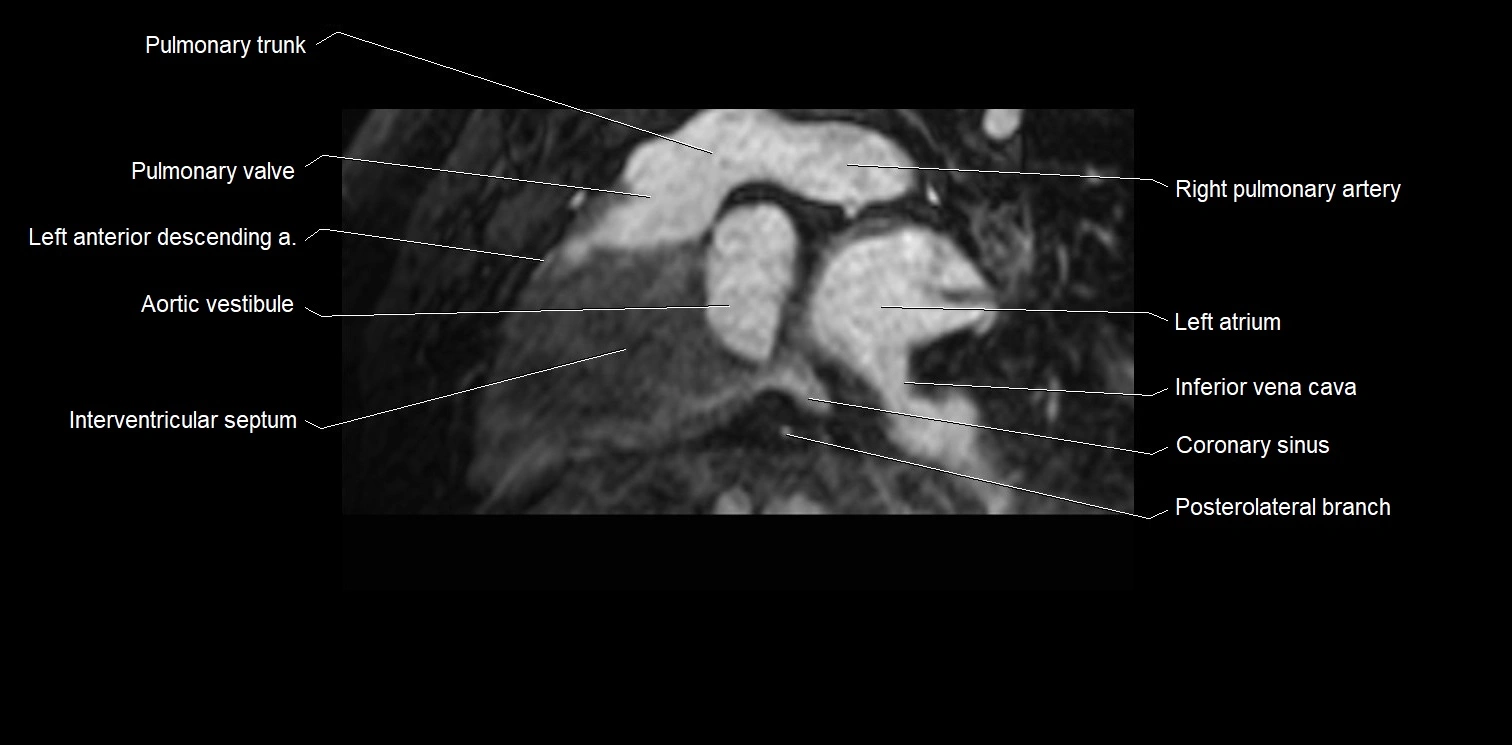

- Aortic vestibule

- Coronary sinus

- Inferior vena cava

- Interventricular Septum

- Pulmonary trunk

- Pulmonary valve

- Right pulmonary artery